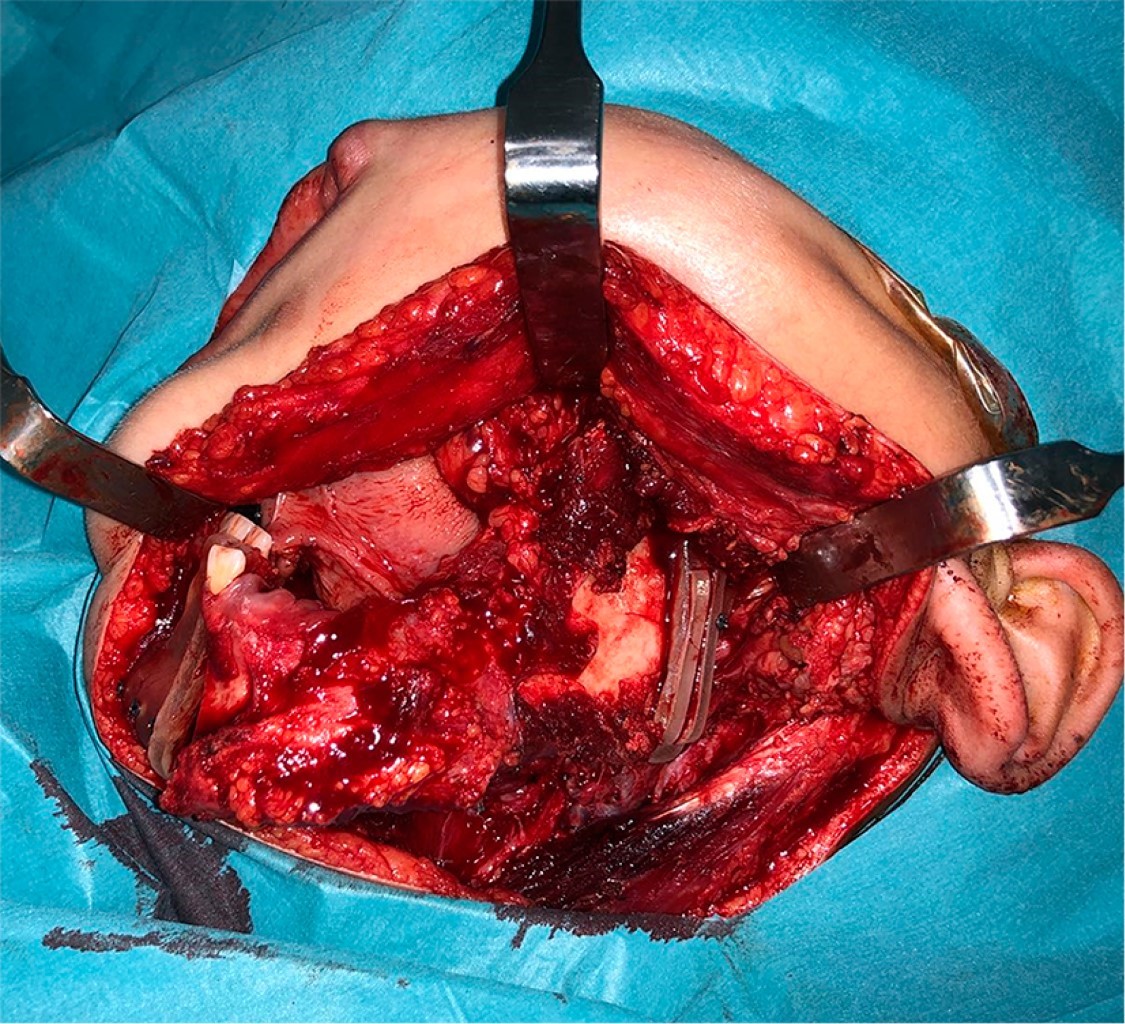

Introduction: Oral cavity squamous cell carcinoma is a frequent entity in adult malignant head and neck pathology; however, it is extremely rare in pediatric age. The treatment and reconstruction of pediatric patients is a challenge due to its high complexity and the few cases described to date in the literature. Material and methods: A clinical case of mandibular squamous cell carcinoma in a pediatric patient is presented. Diagnosis is made by histopathological study and radiological tests, and a virtual planning for mandibular reconstruction is performed. A review of the literature is performed since it is a rare entity. Results: A 9-year-old male of Asian origin came to our office for clinical symptoms of suppuration in the left mandibular region close to the first definitive molar, of approximately 2 months of evolution. A biopsy was performed with an anatomopathological result of squamous cell carcinoma. The case was presented to the Head and Neck Tumors Committee and surgical treatment was decided: left segmental mandibulectomy with oncologic safety margins, left anterolateral functional cervical dissection and reconstruction with microvascularized fibula flap fixed with titanium rod. Cutting guides and virtual planning were used. At 24 months postoperative follow-up there was no locoregional or distant recurrence. Conclusions: Oral cavity squamous cell carcinoma in pediatric age has a low incidence, requiring optimal management and reconstruction. The fibula flap could be the most indicated option for mandibular reconstruction in children. The preservation of the mandibular condyle could favor the mandibular growth of the patient during development.

Figure 3